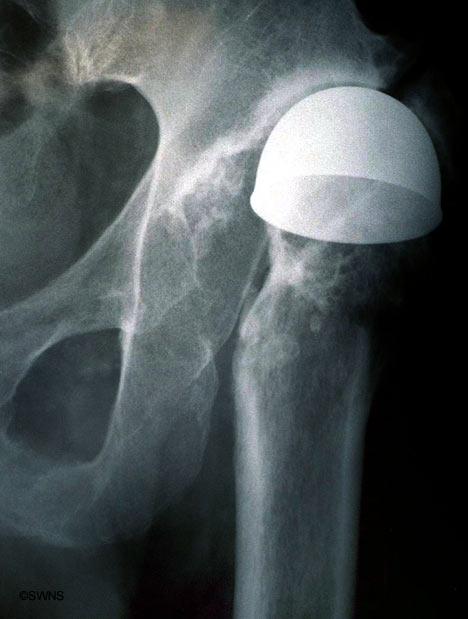

[Ortho] Эндопротез тазобедренного сустава.

Уважаемые коллеги! Вот такой вот рисурфейс. Что делать? Какой прогноз

выживаемости эндопротеза? И что по этому поводу пишут в DailyMail

http://www.dailymail.co.uk/news/article-478779/War-veteran-walks-record-books-60-year-old-hip-replacement.html